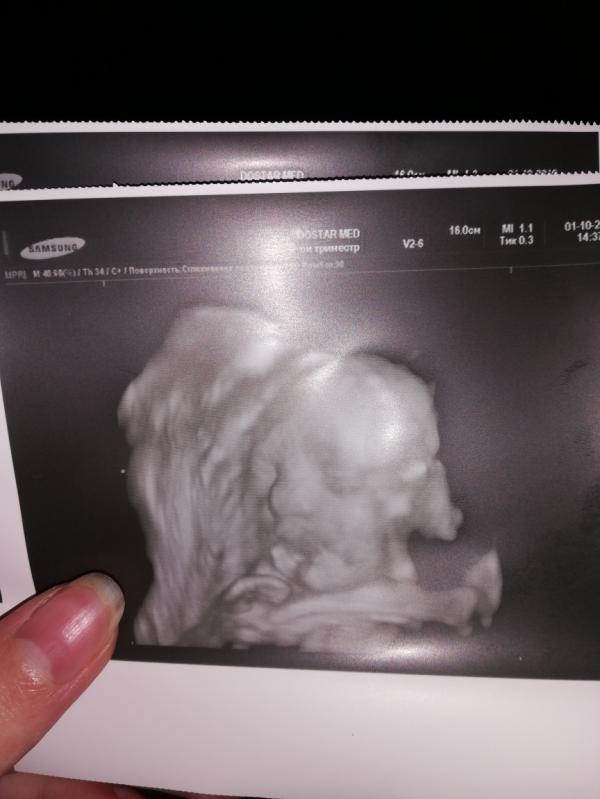

post image 1

Сходила сегодня к Раченковой, она такая классная, спасибо что посоветовали) наша девочка с длинными ногами😃 закрывает ножкой лицо, вся в меня) я тоже родилась с длинными ногами) вообщем советую её теперь всем) не дорого и все внимательно ❤️❤️❤️❤️